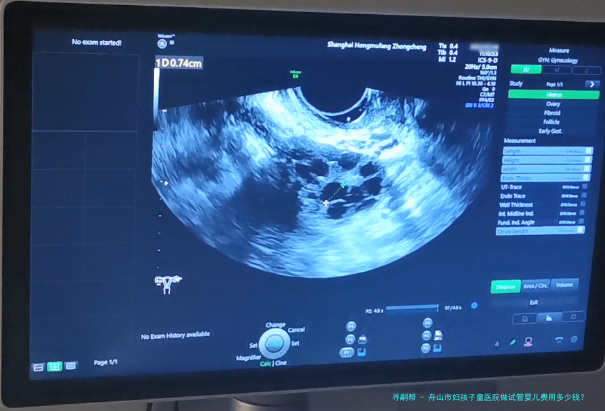

舟山市妇孩子童医院做试管婴儿费用多少钱?

希望拥有本人的宝宝,但因为诸多原因无从自然受孕,试管婴儿就成为无数家庭的曙光。舟山市作为一个享有许多优质医疗机构之处,也提供着完备的试管婴儿服务。哪样舟山市妇孩子童医院做试管婴儿费用多少钱?成功率怎样呢?